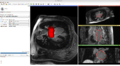

The registration is delivered as a Extension module for Slicer3. It can be installed from the Extension manager. Below in Figure R1 we show the GUI of the module. We need to feed the pre/post-MRI and pre/post-Endocardium images. The module then compute the registration from the post-op MRI to the pre-op MRI.

GUI and one case screenshot